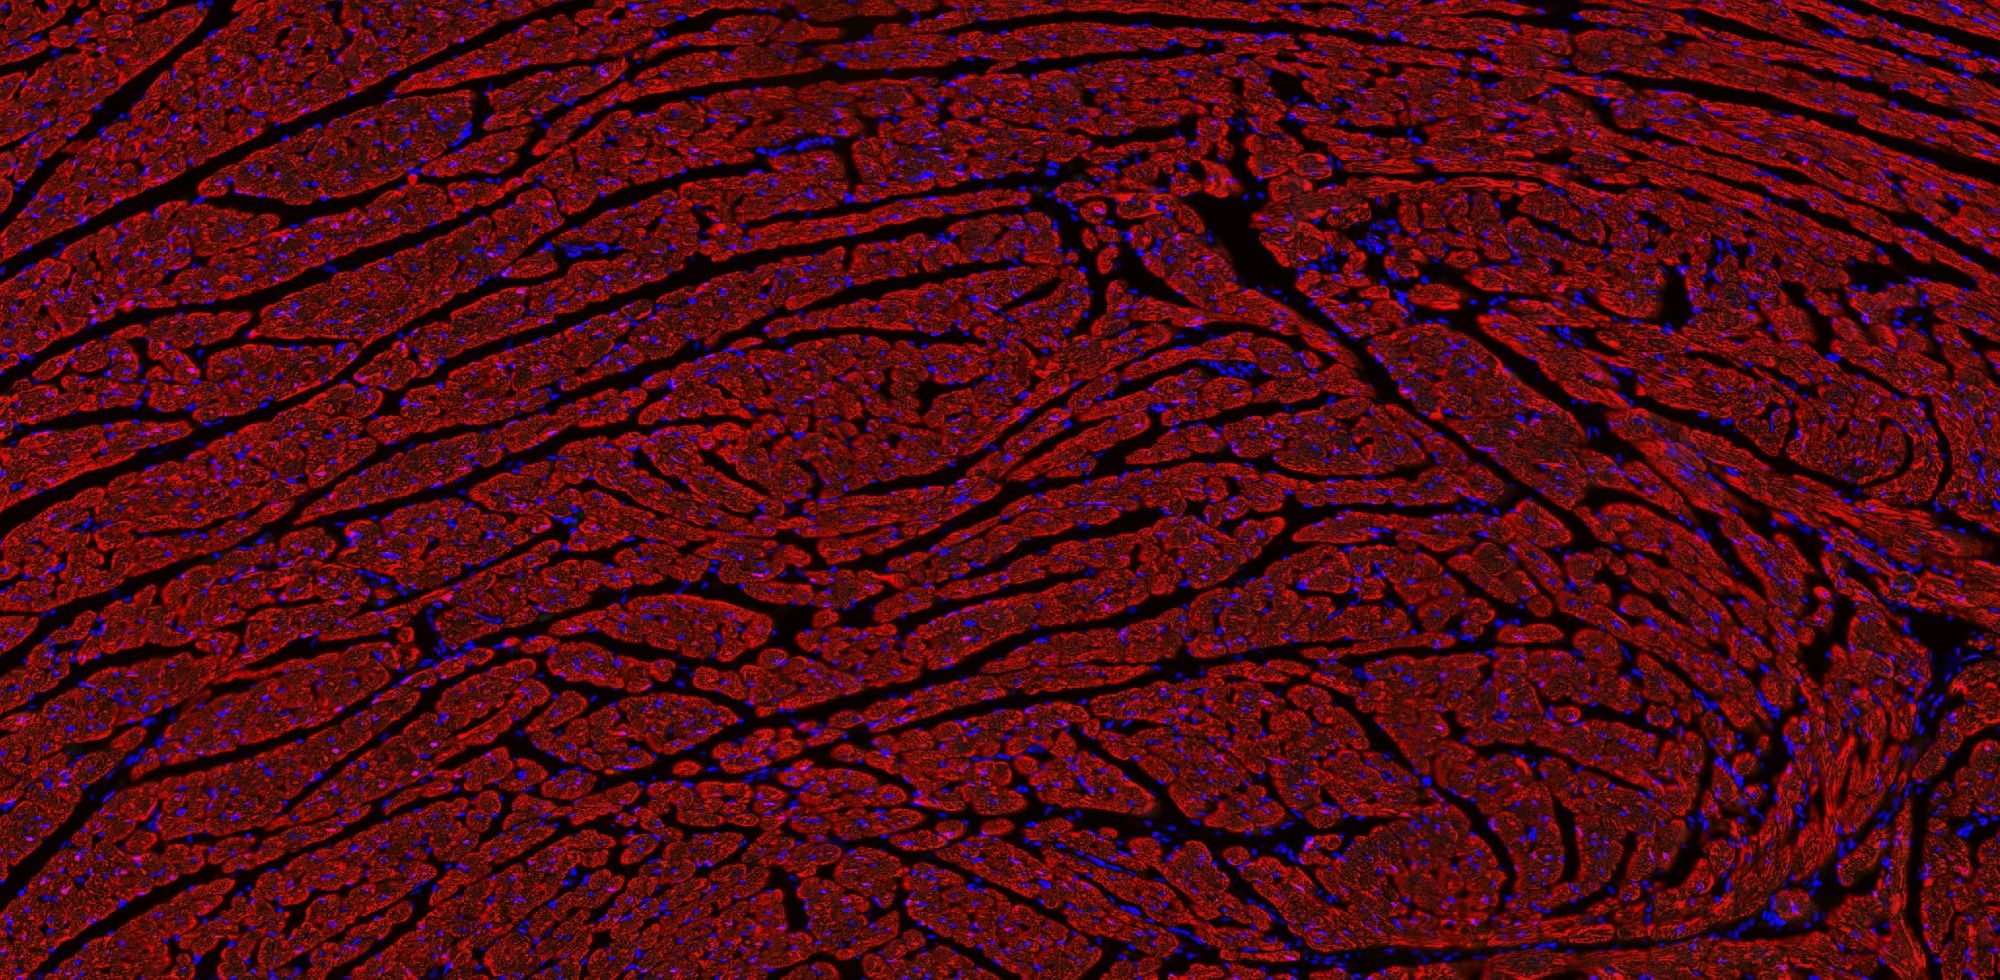

實驗介紹

【技術原理】

免疫學的基本反應是抗原-抗體反應。由于抗原抗體反應具有高度的特異性,所以當抗原抗體發生反應時,只要知道其中的一個因素,就可以查出另一個因素。免疫熒光技術就是將不影響抗原抗體活性的熒光色素標記在抗體(或抗原)上,與其相應的抗原(或抗體)結合后,在熒光顯微鏡下呈現一種特異性熒光反應。

【實驗流程】

案例展示